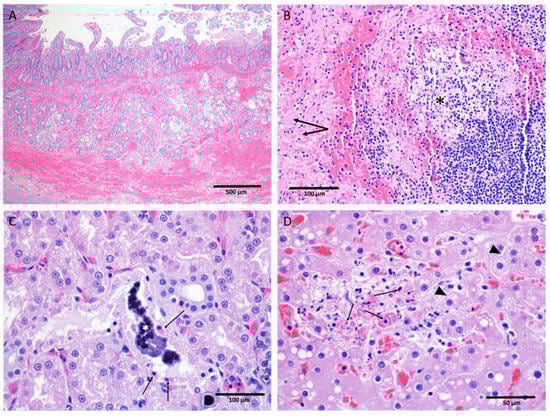

3.8. Anatomic Pathology

Key gross and microscopic lesions included, but were not limited to, the following: macular skin rash, duodenal hemorrhage, lymphocytolysis, renal tubular necrosis with mineralization, splenic fibrin deposition, and hepatocellular degeneration and necrosis (Figure 10). All EBOV-exposed nonsurvivors had positive IHC and/or ISH results in liver, kidney, spleen, lung, heart, intestine, inoculation site, inguinal lymph node, male and female reproductive tissues, eyes, and other tissues.

No liver degeneration or necrosis was observed in the EBOV-exposed survivor. The liver of this animal was microscopically similar to those of the mock-exposed animals, with no inflammation or inclusions. In contrast, 5 of 11 EBOV-exposed nonsurvivors had pale and/or friable liver upon gross examination, 11 of 11 animals had mild to marked liver degeneration and necrosis, and 10 of 11 had notable inflammation (Figure 10D).

Overall, mock-exposed animals had normal spleen microscopically. However, the spleen of the EBOV-exposed survivor exhibited moderate lymphoid follicular hyperplasia. The spleen of all 11 EBOV-exposed nonsurvivors had numerous manifestations of disease, including lymphoid depletion, lymphocytolysis, marginal zone congestion, follicular hemorrhage within the white pulp, and fibrin deposition within the red pulp (Figure 10B).

The mock-exposed animals and the EBOV-exposed survivor had kidneys that generally appeared normal with the exception of mononuclear cell infiltrates in three mock-exposed animals. The kidneys of 11 of 11 EBOV-exposed nonsurvivors, however, displayed renal tubular degeneration, necrosis, mineralization, and fibrin thrombi (Figure 10C).

Hemorrhage of the duodenum and related gastrointestinal tract abnormalities were observed in 9 of 11 EBOV-exposed nonsurvivors (Figure 10A).